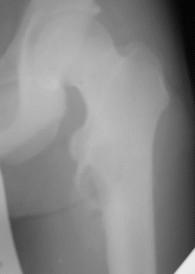

Обратился парень 15ти лет с жалобами на боли в левом коленном суставе. При обследовании обнаружена опухоль в в/з левой бедренной кости.

Проведено КТ заключение( остеохондрома)Подскажите пожалуйста, стоит ли сделать биопсию перед операцией .Кокой операционный доступ и технику операции Вы посоветуете.

Rg

Мне кажется, что это не очень похоже на остеохондрому. Может быть неоссифицированная фиброма? Думаю что перед принятием решения об одномоментной резекции либо о трепанбиопсии стоит более детально уточнить рентгенологический диагноз. Вполне может быть что и тактика изменится на выжидательную. У вас есть более качественные снимки РГ и КТ?

По снимку, хоть и не очень хорошего качества,похожн на кисту, гигантоклеточную опухоль, нельзя исключить саркому Юинга. Важно КТ и клиника.